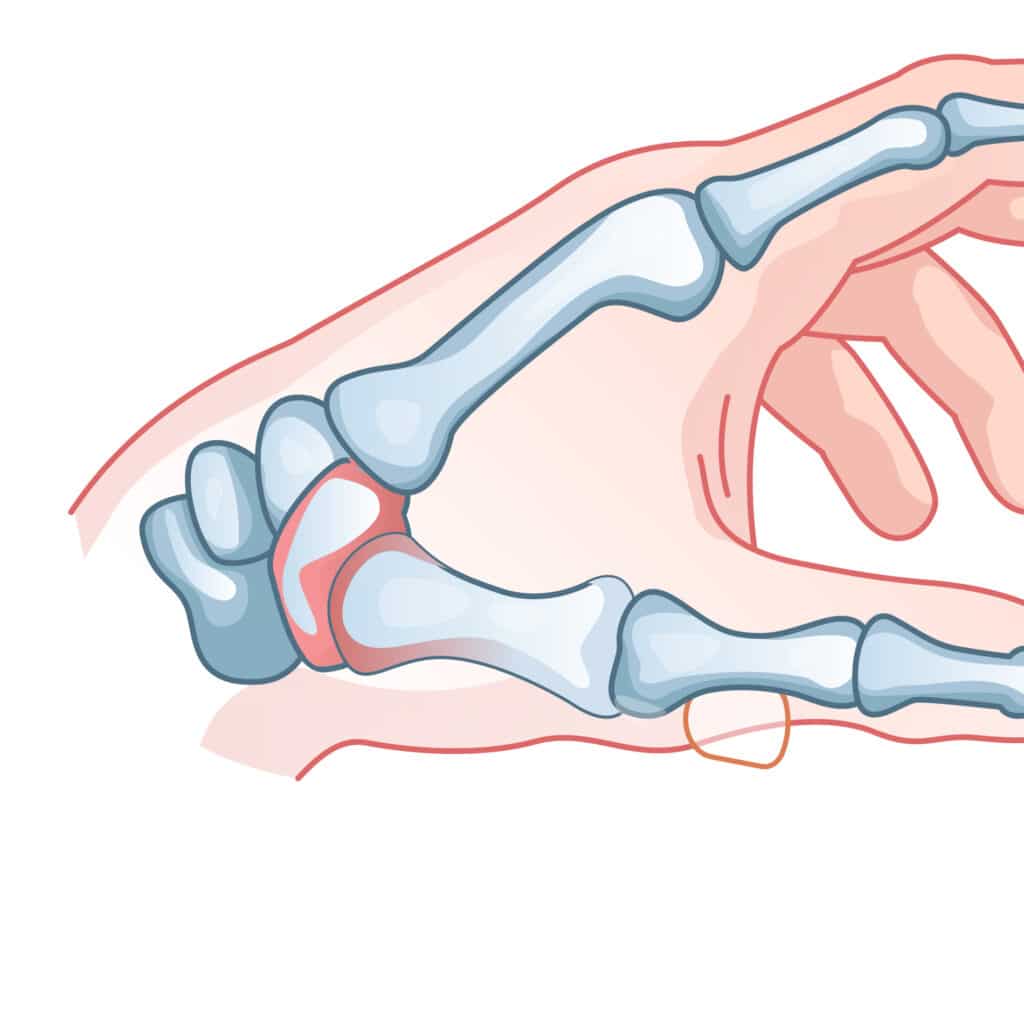

Finger Dislocation

Collateral Ligament Tear